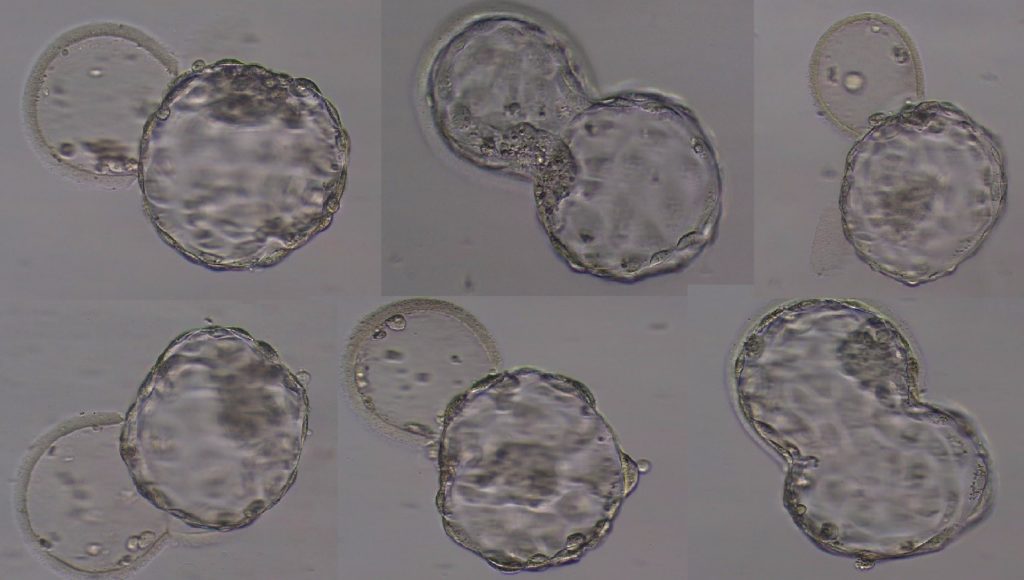

- Culture toujours sur blastocyste (J5) dans un incubateur TimeLapse avec contrôle d’identité par puce de radiofréquence (RI IVFWitness) pour éviter l’erreur humaine.

3) 4 blastocystes garantis au minimum

- FIV Obradors garantit l’obtention d’au moins 4 blastocystes, bien que le but soit d’en obtenir le plus possible.